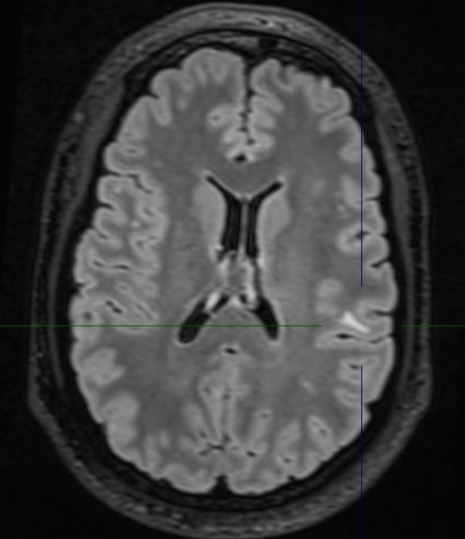

The MRI demonstrates a juxta-cortical, linear lesion in the white matter of the left post central gyrus extending medially to above the insular cortex. There is no mass effect and no enhancement. The nature of the lesion is unclear and does not relate to any of his symptomatology. His loss of consciousness almost certainly was related to a very large binge on alcohol, with very high blood alcohol levels. There is no history of any right facial or any other sensory symptomatology, nor of any episodic or persistent language dysfunction. There is no history of previous cranial trauma. His perinatal and developmental history is unremarkable.

In addition to the above lesion there are a few other punctate white matter lesions. It is presumed that these are old and have been discovered coincidentally as they do not relate to any past or recent symptomatology and are therefore "asymptomatic". I discussed the case with experienced neuroradiologist who reports that the lesions appear "innocuous".  The case also makes the point that diagnostic tests may result in a lot of harm; in this instance the patient was effectively "medically deported" within 24 hours of the scan having been done in a highly developed country. If the EEG is misinterpreted, the patient's problems will only be compounded. His EEG was normal for 72 hours; the rationale for performing it for this duration will be discussed at a later stage